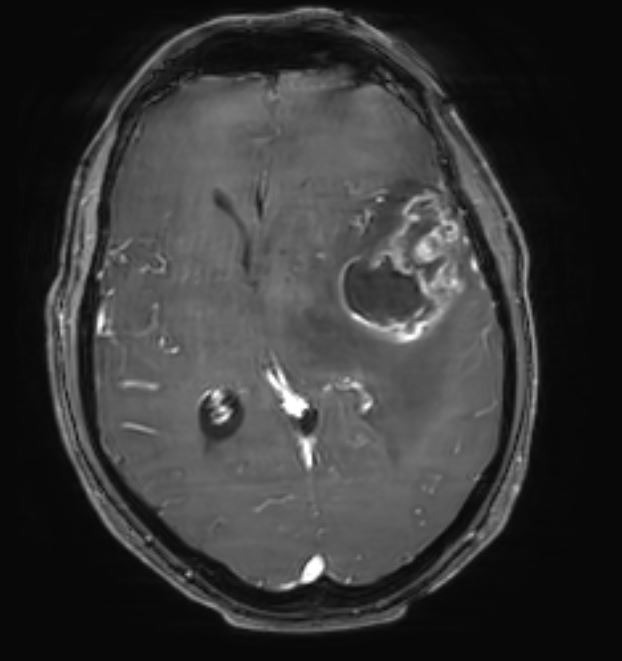

Γλοιοβλάστωμα Δεξιά Κροταφικά

Ασθενής γυναίκα, 67 ετών παρουσίασε επιληπτική κρίση. Η μαγνητική τομογραφία ανέδειξε ευμεγέθη χωροκατακτητική εξεργασία δεξιά κροταφικά με σημαντικό περιεστιακό οίδημα, ύποπτη για κακόηθες γλοίωμα. Διενεργήθη δεξιά